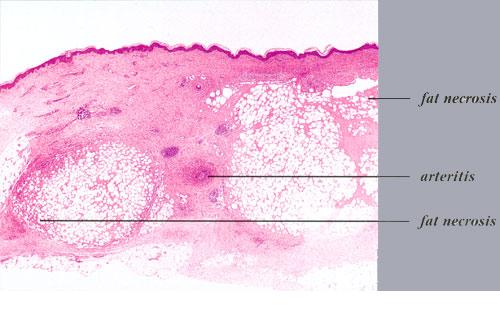

Nodular vasculitis = التهاب الاوعية العقيدي